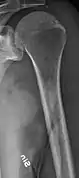

Multiple myeloma in the upper arm

Humerus with multiple myeloma lesions

Same humerus before, with just subtle lesions